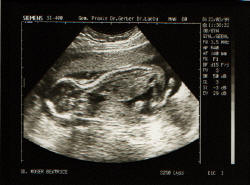

23.03.1999

Hier bin ich schon etwas deutlicher zu erkennen. O

der etwa nicht !!